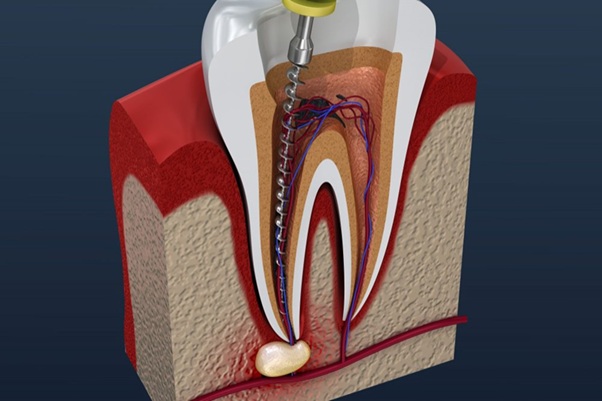

عصبکشی (درمان کانال ریشه) برای نجات دندانی که پالپ آن دچار عفونت یا التهاب شده ضروری است. اما طبیعتاً این فرایند میتواند با درد تورم و استرس همراه باشد. بسیاری از بیماران پیش از مراجعه به دندانپزشک میپرسند: قبل از عصبکشی دندان چه قرصی بخوریم؟ در این مقاله داروهای کلیدی برای تسکین درد کنترل التهاب و کاهش اضطراب را معرفی میکنیم تا تجربهای راحتتر و ایمنتر داشته باشید.

- لیدوکائین یا آرتیکائین بهصورت موضعی روی لثه اعمال میشوند.

- مزیت: تأثیر سریع و متمرکز بدون نیاز به بیهوشی عمومی.

- رادیوگرافی: انجام تصویر برداری قبل از اندو تصویری دقیق از وضعیت ریشه و استخوان فک میدهد.